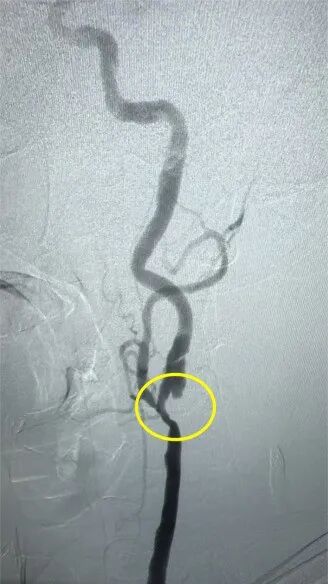

術(shù)前(左)、術(shù)后(右)的血管造影檢查

1個(gè)月前,60歲的陳大爺在家里出現(xiàn)反復(fù)發(fā)作的短暫性頭暈,伴有黑朦,于是前往惠州三院神經(jīng)醫(yī)學(xué)中心就診,經(jīng)檢查后診斷為短暫性大腦缺血性發(fā)作,責(zé)任血管則是左側(cè)頸內(nèi)動脈狹窄。進(jìn)一步完善頸動脈超聲檢查后,醫(yī)生發(fā)現(xiàn)陳大爺狹窄段長,伴夾層、潰瘍斑塊且不穩(wěn)定,發(fā)生急性腦血管意外的風(fēng)險(xiǎn)極高!

神經(jīng)外科腦血管病區(qū)景英朝主任與患者及家屬溝通后,建議住院行手術(shù)治療??紤]到患者長期患有高血壓、糖尿病等基礎(chǔ)疾病,醫(yī)生決定采用介入手術(shù)方案——頸內(nèi)動脈狹窄支架置入術(shù)。

在麻醉科、介入室、放射科及電生理團(tuán)隊(duì)的通力合作下,陳大爺如期進(jìn)行了介入手術(shù)。術(shù)后,陳大爺恢復(fù)良好,無手術(shù)并發(fā)癥,術(shù)后3天就出院了,頭暈、眼前黑朦癥狀再未發(fā)生,自訴頭腦也比以前清醒了。復(fù)診時(shí),陳大爺特意送上準(zhǔn)備已久的錦旗,對醫(yī)護(hù)團(tuán)隊(duì)的精心治療及細(xì)致護(hù)理表示感謝。